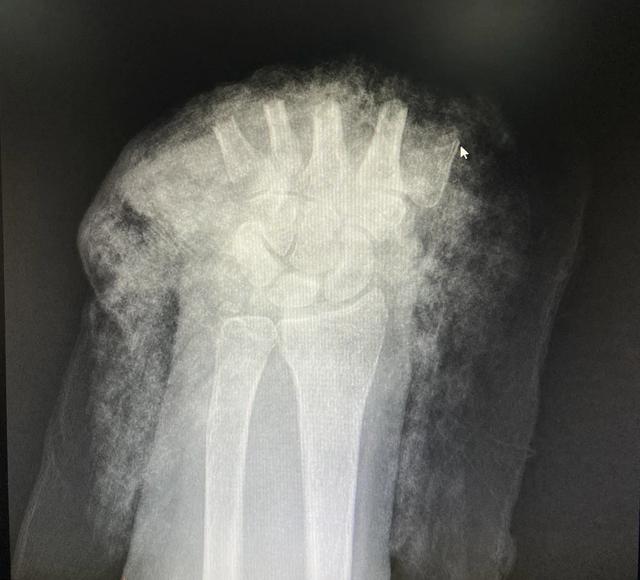

断掌正面CT图

树兰杭州医院医生奋战 5 小时,断掌残垣成功再植

“因牵牛而导致断手的病例还是头一次看到。”树兰(杭州)医院手足显微外科黎斌副主任医师接诊后表示:“伤者由于手掌被麻绳勒紧,受到前后牵拉力同时作用而造成手掌骨头、肌腱及神经组织断裂,属于非常严重的旋转撕脱离断伤。”

黎斌副主任介绍介绍,手足显微外科经常会接诊被机器或者刀具砍伤的手部受损,断面比较整齐,但张奶奶这种撕扯伤有很多缺损组织,因拉扯被抽出的肌腱长度达20多厘米,比砍断更严重,大大增加了再植手术的难度,因此当时伤者送到医院时已经面临截肢的危险。